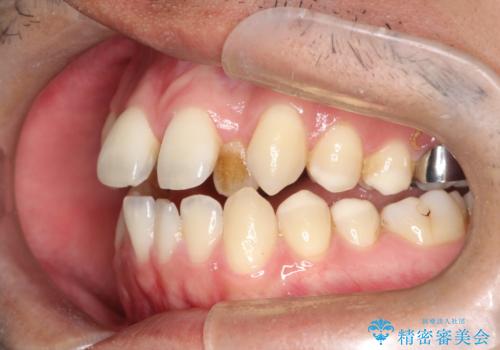

【MSE+インビザライン】前歯のガタガタ

- 前歯の凸凹を主訴に来院されました。

上の歯のアーチが狭窄していたため、骨の幅を広くするためにMSE(急速拡大装置)を使用してからインビザライン にて治療を行いました。

MSE(急速拡大装置)を用いたことで、短期間で奥歯の噛み合わせもしっかりと治すことができました。